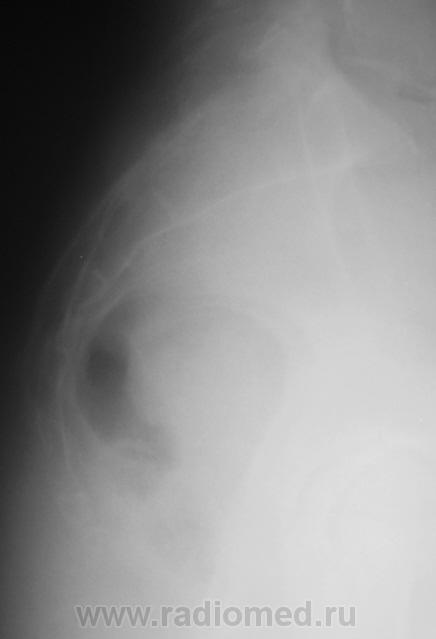

Пациент направлен на рентгенографию крестца и копчика с диагнозом "Перелом".

Похоже на перелом S4. Я, конечно, не поверю, что Вы обошлись только боковой. Опять интрига?

Нет никакой интриги. Просто снимок, произведенный в одной боковой проекции (не у нас) был дан для описания.

Если смотреть по задней пов-ти - то все ровно. Но я думаю, что нужно смотреть все-таки по передней, а там есть ступенька в S4. И если была травма и есть клиника - грех не поставить перелом. Хотя это настолько банально, что, я думаю, Вы бы его не выставили.